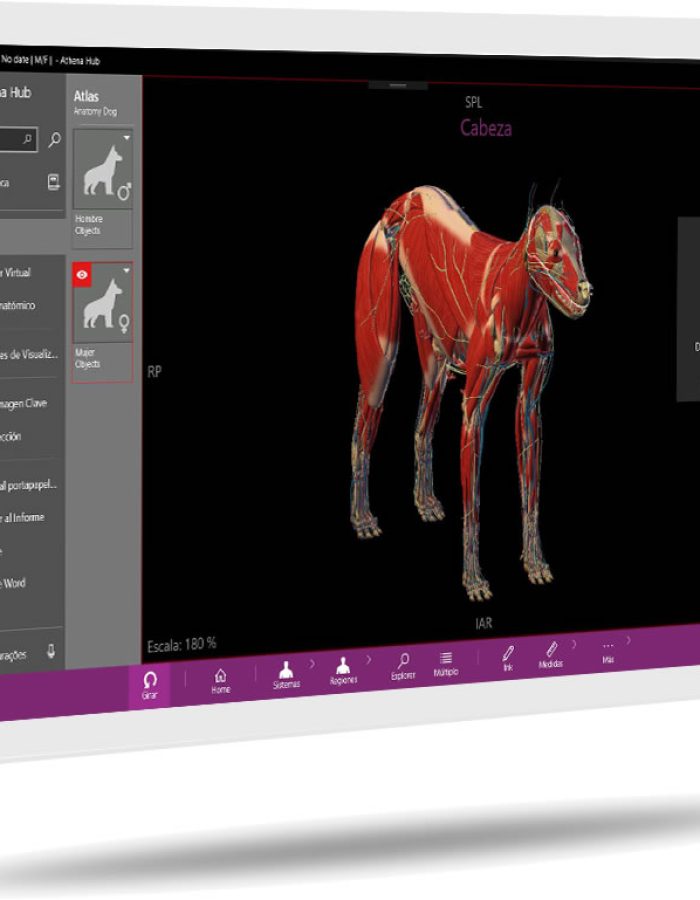

_ Athena es un poderoso software de anatomía 3D de fácil instalación.

_ También funciona como software libre para usarlo en el hardware que la institución tenga.

_ Tenemos más módulos que nuestros competidores más cercanos, con mayor tecnología y a mitad de precio.